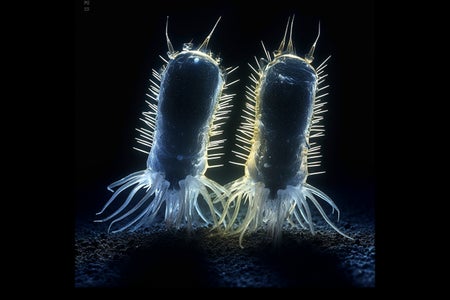

Could Endometriosis Be Caused by Bacteria? Study Offers Fresh Clues

A link between endometriosis and bacterial infection suggests a potential way to treat the painful disorder